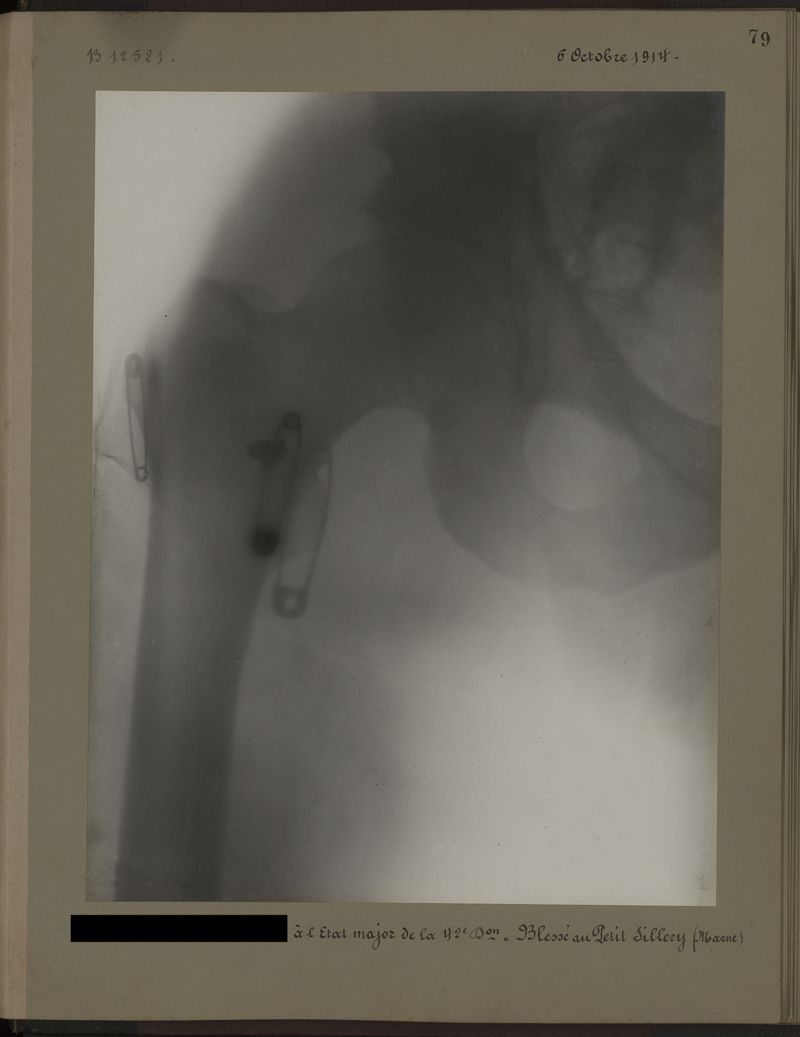

Deux albums de radiographies de la Première Guerre mondiale. Collection du laboratoire central de radiographie de la Salpêtrière. Deuxième album.

1915.